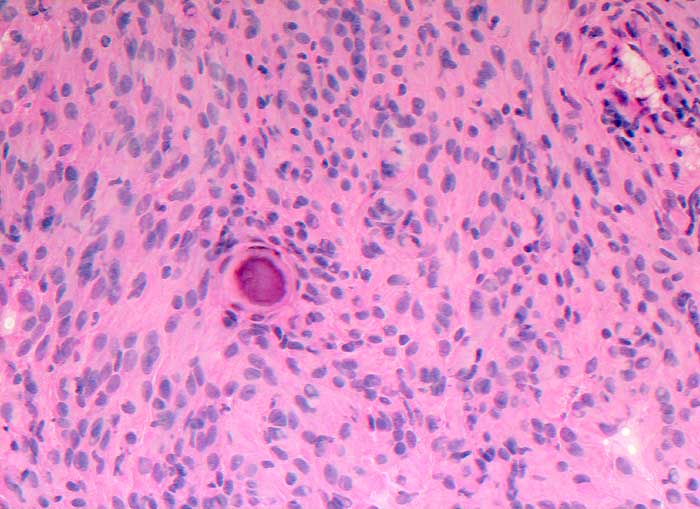

Abstriche und Waschflüssigkeit von Meningeomen sind meist auffallend zellreich. Die Zellen sind in pseudoepithelialen Verbänden gelagert. Charakteristisch sind Psammomkörperchen und zwiebelschalenartig geschichtete meningotheliale Zellkomplexe. Bei bestimmten Meningeomsubtypen sind diese Zellkomplexe jedoch nicht leicht auffindbar. Die Kerne enthalten gelegentlich intranukleäre Vakuolen. Die Zellen anaplastischer Meningeome sind stärker dissoziiert, die Kerne sind hyperchromatisch und pleomorph, Mitosen sind vermehrt.